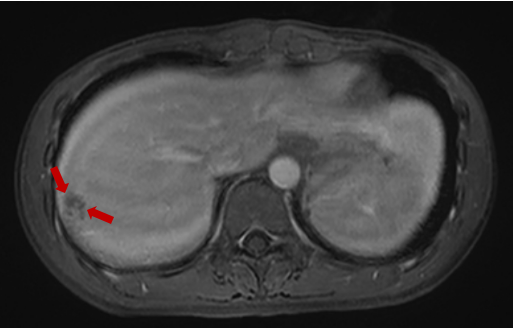

随后,入院查血常规提示嗜酸性粒细胞百分比大于40%,转氨酶明显升高,CT检查提示肝右叶占位性病变。上腹部磁共振增强提示肝右叶包膜下多发液性信号。肥大反应提示丙型副伤寒1:320,考虑沙门菌感染,这是一种由沙门氏菌属细菌引起的常见食源性疾病,可以通过受污染的食物或水传播。

磁共振显示:肝右叶包膜下见多处团片状、楔形病灶。